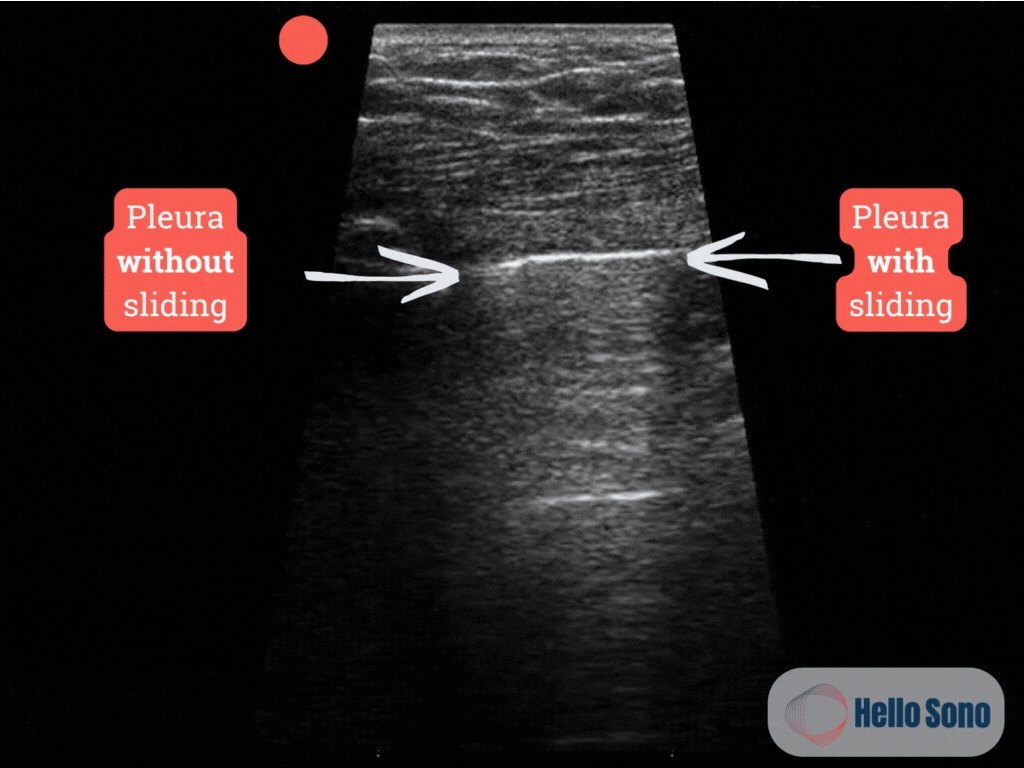

Clip 1: This ultrasound clip shows the apex of the right lung. The pleura appears as a bright white (hyperechoic) horizontal line near the top of the image. You can observe pleural sliding on the right side of the image, while the left side shows no sliding.

The ultrasound clip reveals a lung point, the exact location where normal lung with pleural sliding transitions to an area without sliding. This “on-off” pattern is pathognomonic for pneumothorax. On one side of the image, shimmering pleural sliding confirms lung apposition; on the other side, the absence of sliding confirms the presence of air in the pleural space.  See annotated clip (Clip 2).

Although complete absence of lung sliding may suggest a pneumothorax, it is not specific. Other conditions, such as pleural adhesions, large subpleural blebs, subpleural pneumonia, or scarring from prior infection or surgery, can also eliminate lung sliding. Therefore, identifying the lung point is key as it confirms the presence of a pneumothorax with high specificity.

Clip 2: Ultrasound clip showing the lung point at the apex of the right lung with annotations.